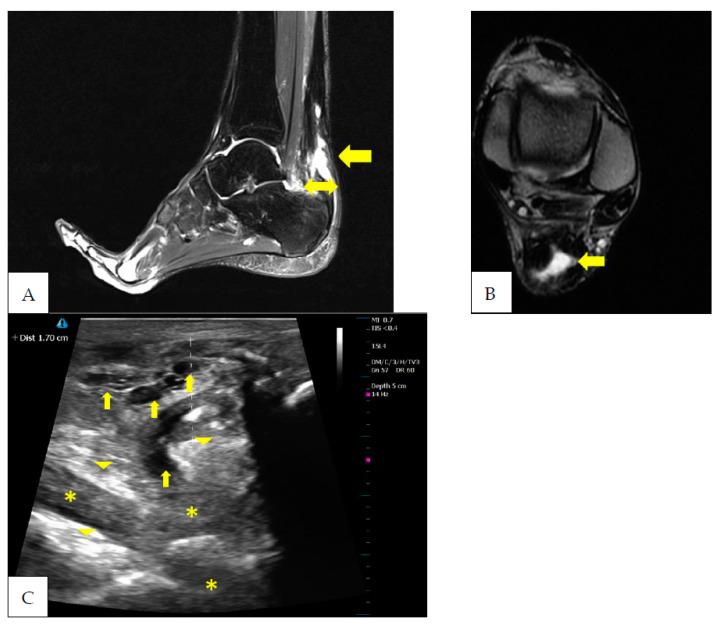

After Achilles tendon tenorraphy, tendon tissue undergoes a long period of biological healing. During this period, tissue turnover shows heterogeneity between its peripheral and central regions. This case report concerns the description of the tendon healing process of an athlete who underwent an Achilles tendon tenorraphy. As the reparative processes progressed, magnetic resonance imaging (MRI) showed centralization of the hyperintensity area and the tendon assumed a doughnut-like appearance. At the same time, ultrasound (US) assessment showed a progressive reorganization of the tendon fibrillar structure. Therefore, for the athlete, MRI and US assessment together represent a useful tool for the decision-making process after Achilles tendon tenorraphy.